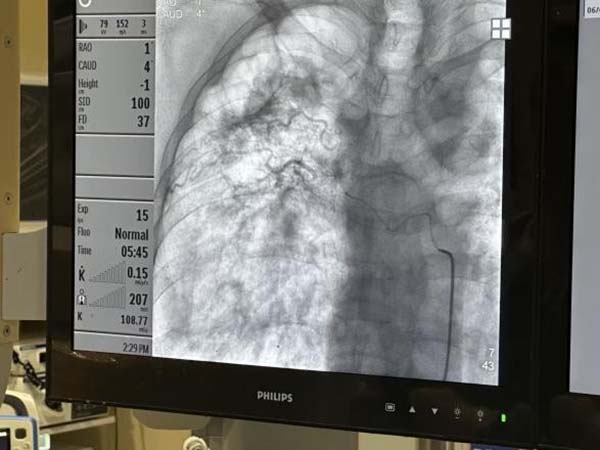

中心投入运行的号角刚刚吹响,一位因既往重症肺结核导致“毁损肺”的患者被紧急送入我院急诊科。影像学检查显示其肺部结构严重破坏,肺血管广泛畸形、迁曲、紊乱,如同布满了“不定时炸弹”的危险雷区,常规止血手段效果有限且风险极高。患者迅速由急诊转入呼吸科,咯血中心团队立即启动应急响应。在中心负责人王东昌带领下,介入诊疗团队凭借高超的血管造影技术和三维重建能力,在错综复杂的血管网络中精准定位到多支出血的“罪魁祸首”。手术台上,医生们屏气凝神,操作导管如臂使指,精准地将栓塞材料送达目标血管,成功实现了对多支畸形出血血管的介入封堵止血。

首战硝烟未散,更严峻的考验骤然降临!一位正在呼吸重症监护室(RICU)接受治疗的患者突发危及生命的大咯血!鲜血瞬间淹没了气道,患者血氧饱和度急剧下降,命悬一线!一场与死神赛跑的“生命保卫战”瞬间打响!RICU医护团队反应神速,立即实施紧急气管插管,建立稳固的人工气道,为后续抢救赢得宝贵时间窗口。插管后第一时间进行床旁气管镜检查,凭借娴熟技术迅速、彻底地清理了主气道及主要支气管内的大量积血凝块,有效恢复了部分通气。患者的生命体征虽暂时稳住,但仍极度脆弱,且完全依赖呼吸机支持。将其安全转运至导管室进行决定性止血手术,是抢救成功的关键,也是前所未有的巨大挑战。中心预先制定的危重患者转运预案即刻启动。在严密监测患者生命体征的前提下,克服重重困难,实现了带呼吸机危重患者的“无缝衔接”安全快速转运,直达介入导管室。专家们争分夺秒进行血管造影,精准定位出血责任血管,并成功实施了血管介入栓塞止血术。当汹涌的出血被成功遏制,监护仪上的生命体征逐渐趋于平稳,整个团队悬着的心才稍稍放下。

连续两场高强度战斗后,中心团队没有丝毫懈怠。第三例挑战随之而来——一位胸外科的住院患者2年前曾因咯血在外院接受过血管介入栓塞治疗,但效果不佳,咯血反复发作。此次病情急剧恶化,不仅出现气道内活动性出血,更合并了右侧大量血胸,病情极其凶险,常规治疗手段捉襟见肘。血管造影结果揭示了严峻的现实,出血范围广泛,累及多支血管分支,血管网络错综复杂,且既往栓塞区域可能存在再通或新生血管。手术难度远超预期!中心的专家们反复分析造影图像,精确识别所有可疑的出血责任血管。根据血管的粗细、走行、出血速度,个性化选择最适宜的栓塞材料。对目标血管进行超选择性插管和精准栓塞,如同进行一场精密的“血管内排雷”。确保所有可疑的出血来源均被有效封堵,达到完全止血的目标。手术最终取得圆满成功!困扰患者多年的复发顽疾、此次凶险的合并出血,被中心团队一举攻克。